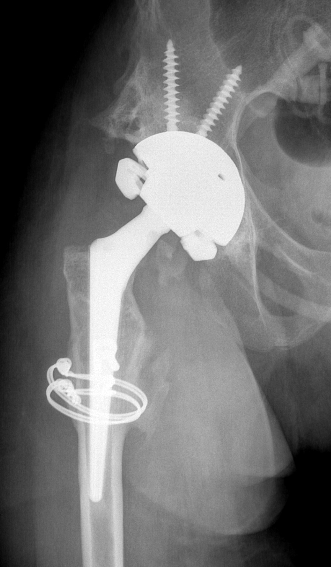

Surgical Excision

Indications

Significant symptoms / reduced ROM

Brooker III / IV

Timing

Mature HO

- cold bone scan

- serum ALP normal

Prophylaxis

Radiotherapy postoperatively as high risk

Technique

Results

Lachiewicz et al J Arthroplasty 2022

- systematic review of 7 studies and 4 patients with grade III/IV HO

- good improvement in ROM

- inconsistent improvement in pain

- irradiation prevented recurrence